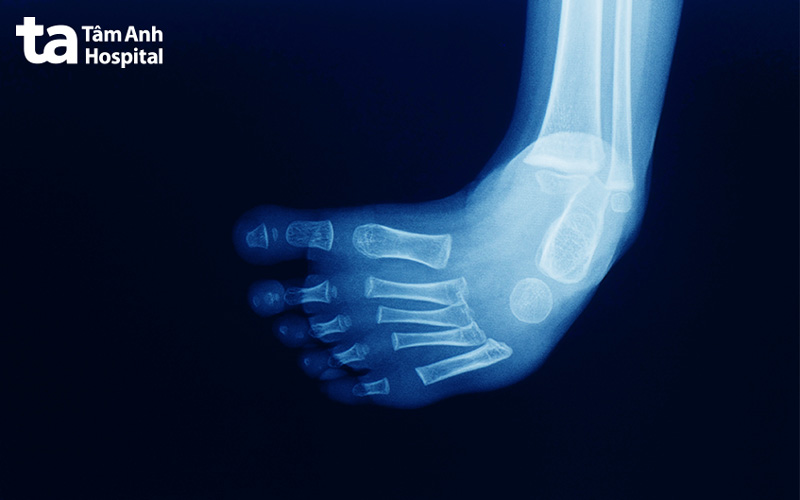

Khi đó, bác sĩ có thể chỉ định người bệnh chụp X-quang hay siêu âm để chẩn đoán chính xác tình trạng chân của bệnh nhi. Đối với trường hợp này, kết quả X-quang cần chụp 2 góc thẳng và nghiêng, chụp cả 2 bên bàn chân của trẻ để so sánh, cụ thể: (4)